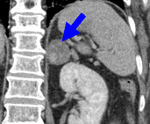

Чаще всего инциденталомы диагностируются в процессе визуализирующих исследований брюшной полости и забрюшинного пространства (УЗИ, КТ, МРТ), выполняемых по поводу других заболеваний.

При выявлении того или иного опухолевого образования надпочечников на следующем этапе уточняется его гормональная активность и гистологическая структура. С этой целью выполняется определение базального уровня гормонов надпочечников (кортизола, альдостерона, эстрогенов, андрогенов, катехоламинов) и их содержания в крови в ответ на стимулирующие пробы. Кроме гормональных тестов, при выявлении инциденталом проводится исследование уровня калия крови (для исключения гиперальдостеронизма), дегидроэпиандростерон сульфата - маркера секреции андрогенов.

В рамках диагностики инциденталом выполняется селективная ангиография (артериография, флебография), доплерография надпочечников, радионуклидная сцинтиграфия, экскреторная урография. Вопрос о тактике лечения при случайных инциденталомах решается по результатам тонкоигольной аспирационной биопсии надпочечника. Несмотря на высокую информативность биопсии, применение ее ограничено в связи с высокой вероятностью развития осложнений (гемоторакса, пневмоторакса, кровотечения, гематурии, гематомы почечной или печеночной паренхимы, панкреатита, инфекции ).